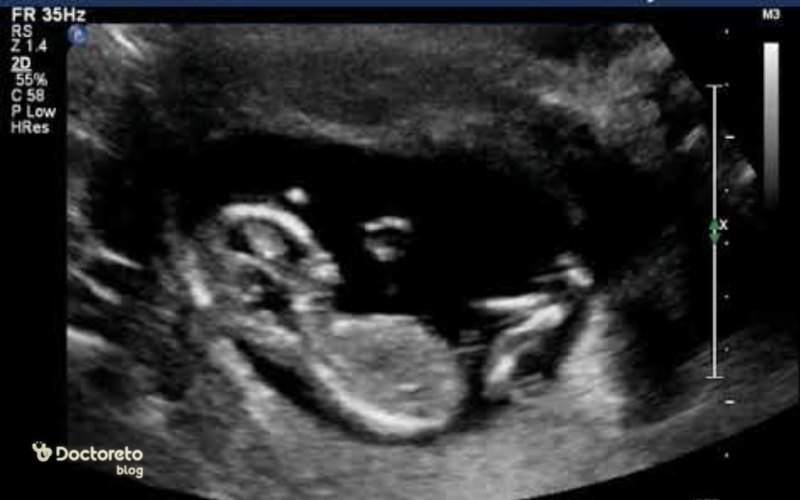

سونوگرافی در هفته ۱۳ بارداری

اگر پزشک در هفته دوازدهم بارداری سونوگرافی تجویز نکرده باشد، در این هفته باید انجام شود. ممکن است در این سونوگرافی بتوانید جنسیت جنین را متوجه شوید اما هنوز اندامهای جنسی جنین بسیار کوچک است. به همین دلیل احتمالا پزشک در هفته ۱۸ تا ۲۲ بارداری جنسیت را اعلام میکند.

در هفته سیزدهم، اندامهای جنسی جنین هنوز به اندازهای بزرگ نشدهاند که تعیین جنسیت قطعی از طریق سونوگرافی امکانپذیر باشد. معمولا تشخیص قطعی جنسیت از هفته ۱۸ به بعد انجام میشود.